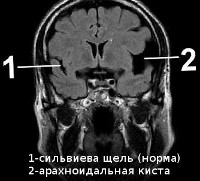

В зависимости от места расположения выделяют арахноидальную и внутримозговую (церебральную) кисту. Первая локализуется в мозговых оболочках и образуется за счет скопления цереброспинальной жидкости в местах их врожденной дупликатуры или спаек, сформировавшихся в результате различных воспалительных процессов. Вторая располагается во внутренних структурах головного мозга и формируется на участке погибшей в результате различных патологических процессов мозговой ткани. Отдельно выделяют также кисту шишковидной железы, кисту сосудистого сплетения, коллоидную и дермоидную кисты.

Арахноидальная киста чаще имеет врожденный или посттравматический характер. Расположена в мозговых оболочках на поверхности мозга. Наполнена цереброспинальной жидкостью. По некоторым данным, до 4% населения имеют арахноидальные кисты головного мозга. Однако клинические проявления наблюдаются лишь в случае большого скопления жидкости в кисте, что может быть связано с продукцией ликвора выстилающими полость кисты клетками. Резкое увеличение размеров кисты угрожает ее разрывом, приводящим к смертельному исходу.